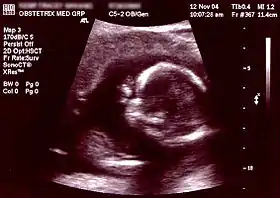

| Non-invasive | Ultrasound detection | Commonly dating scans (sometimes known as booking scans or dating ultrasounds) from 7 weeks to confirm pregnancy dates and look for multiple pregnancies. The specialised nuchal scan at 11–13 weeks may be used to identify higher risks of Downs syndrome. Later morphology scans, also called anatomy ultrasound, from 18 weeks may check for any abnormal development. Additional ultrasounds may be performed if there are any other problems with the pregnancy, or if the pregnancy is post-due. | First or second trimester |